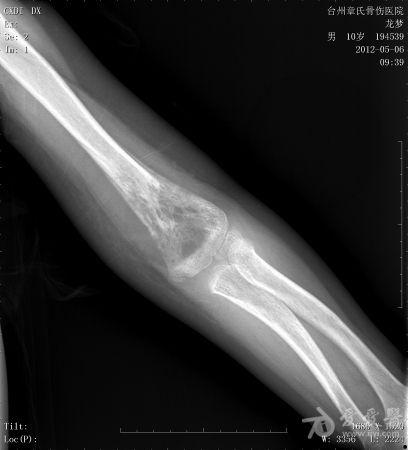

小孩 肱骨骨肿瘤并病理性骨折

年龄:10岁主诉: 右上臂疼痛活动受限20余天现病史: 20余天前摔伤致右肘部疼痛活动不利,曾在外院治疗,X线:右肘部未见明显异常。肘关节活动尚可,于活血化瘀,消肿止痛治疗。20余天疼痛未见明显好转,肘关节活动不利,***就诊。既往史: 既往健康

体格检查: 一般状况好,发育良好,营养中等。头颅五官胸腹未见异常。右肘部,右上臂下端肿胀,压痛、纵向叩击痛(+),局部肤温增高。肘关节固定于约40°,背伸约20°,肘屈约100°,表面无血管充盈,无色素沉着。右上肢皮肤感觉正常,右桡动脉搏动正常。

初步诊断: 左肱骨下端骨肿瘤X线检查显示左肱骨中上段有虫蚀样 低密度改变,局部硬化,可见骨膜反应,病理性骨折鉴别诊断: 动脉瘤样骨囊肿,骨结核诊疗过程:

讨论内容:患者病史极短,摔伤后检查未见明显异常,初次就诊,复诊时间间隔约16天,未留下初次就诊的X线资料,仅感觉肱骨下端较上段骨密度稍减低。

患者是否为骨肉瘤,如何能及早发现诊治,是否需要截肢。

骨肉瘤多见于小儿,多发生于干骨端,常见于股骨远端和胫骨近端。骨肉瘤的X线表现:⒈骨质破坏⒉肿瘤骨⒊肿瘤软骨钙化⒋软组织肿块⒌骨膜反应和Codman三角。动脉瘤样骨囊肿多发生于10-20岁,可发生生于长骨和脊柱。动脉瘤样骨囊肿的X线表现为长骨干骺端的溶骨性、偏心性骨破坏,其偏心向外突出如气球状膨胀,病变呈局限性透亮区,边界清楚,边缘有狭窄的硬化带,其中有不规则的分隔,呈蜂窝状。位于骨中心者,向周围扩张膨胀,呈卵圆形,与骨的纵轴一致。囊肿表面有一薄的骨壳,可有一层薄的骨膜反应。位于脊椎的病变多在脊突、椎板、横突上,亦可膨出于骨外。 根据以上特点和本病例的表现,骨肉瘤可疑。